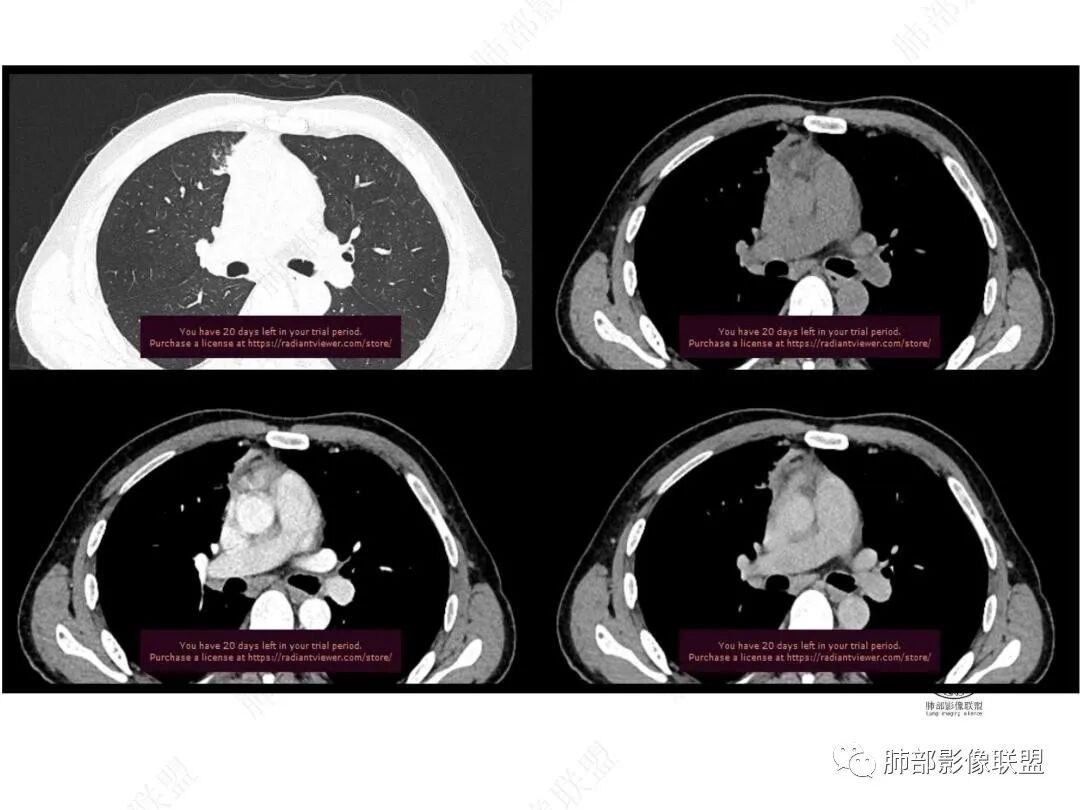

平扫图像

增强图像

右肺上叶前段纵隔旁见团块状影,边缘毛糙,部分直边,支气管进入,管壁增厚,密度均匀,明显强化。考虑炎性病变。纵隔胸膜似有栽桩,腺癌待排。

中年男性,慢性发热3月,白细胞总数及crp升高,右肺上叶实变影,边缘平直为主,似乎均匀强化,血管进入后截断,考虑血管相关性曲霉感染?

中年男性,前纵膈旁团块,边缘平直,周围可见模糊的磨玻璃影,相邻支气管壁增厚,部分支气管进入病灶后阻塞,增强病灶渐进性强化,肝右叶见边缘不清的低密度影,增强渐进性强化。结合实验室检查,总体考虑炎性病变,自免性炎症?血管炎?

中年男性,右前纵隔旁不规则实变影,局部支气管进入后截断,病灶渐进性强化。肝脏右叶低密度灶,边界不清,呈明显渐进性强化。IMT?

右肺上叶纵膈旁团片,边缘毛糙,平直为主,其内见空洞,周围卫星灶,支气管进入阻塞,渐进强化,肝右叶低密度影,边界不清,渐进强化,考虑炎性病变,结核?

男,49,低热3月。胸部CT:右肺上叶前段纵隔旁见团片影,部分边缘毛糙,部分平直、内收,邻近卫星灶、晕征,重建L征?支气管管壁增厚、进入后堵塞;纵隔可见肿大淋巴结;病灶密度较均匀,中度强化。肝脏片状低密度影,边缘模糊。考虑炎性病变,PC?TB?鉴别腺癌。

中年男性,反复低热3月伴近期乏力及右上腹隐痛,白细胞,中性粒及淀粉样蛋白A增高,PCT不高,IGA、IGg增高,类风湿因子增高,未提供IGg4水平,影像改变,左侧肋骨陈旧性骨折(2020年已存在)右上叶前段胸骨旁的胸膜下新发病灶,支气管进入后一段才堵塞,肺动脉进入,走行自然,未见破坏,明显均匀强化,气管及支气管壁有增厚,钙化,纵隔内淋巴结增大,均匀强化,无坏死,纵隔内脂肪混浊,局部强化,肝内低密度灶,延迟强化(肺内病灶,淋巴结、混浊脂肪,肝内病灶强化均一致,且均为延迟强化)。初步考虑:免疫相关性炎症,IGg4相关炎症可能大,依据:IGA、IGg增高(未提供IGg4,可能是故意隐藏了),类风湿因子增高,炎性指标增高,但PCT不高,细菌感染可能就变小,加上病变同时累及肺、纵隔淋巴结,纵隔内脂肪、肝。

2.右肺上叶纵隔旁新发实性密度病灶,密度均匀,轻度强化,未见空洞、液化坏死及钙化,血管穿行自如,支气管进入后狭窄截止。灶周磨玻璃影边界不清,病灶未见明显分叶毛刺,平直、轻度收缩、周围偶见结节影,但未见树芽征。注意纵隔胸膜侵入或突入比较明确。纵隔淋巴结轻度增大。

3.右肺容易想到的病变有慢性炎症、IGg4相关、新生物(炎性肌纤维母细胞瘤、腺癌等)。但病灶侵入纵隔胸膜应当更符合恶性肿瘤。病程进展及强化等影像特点不支持继发性肺结核。